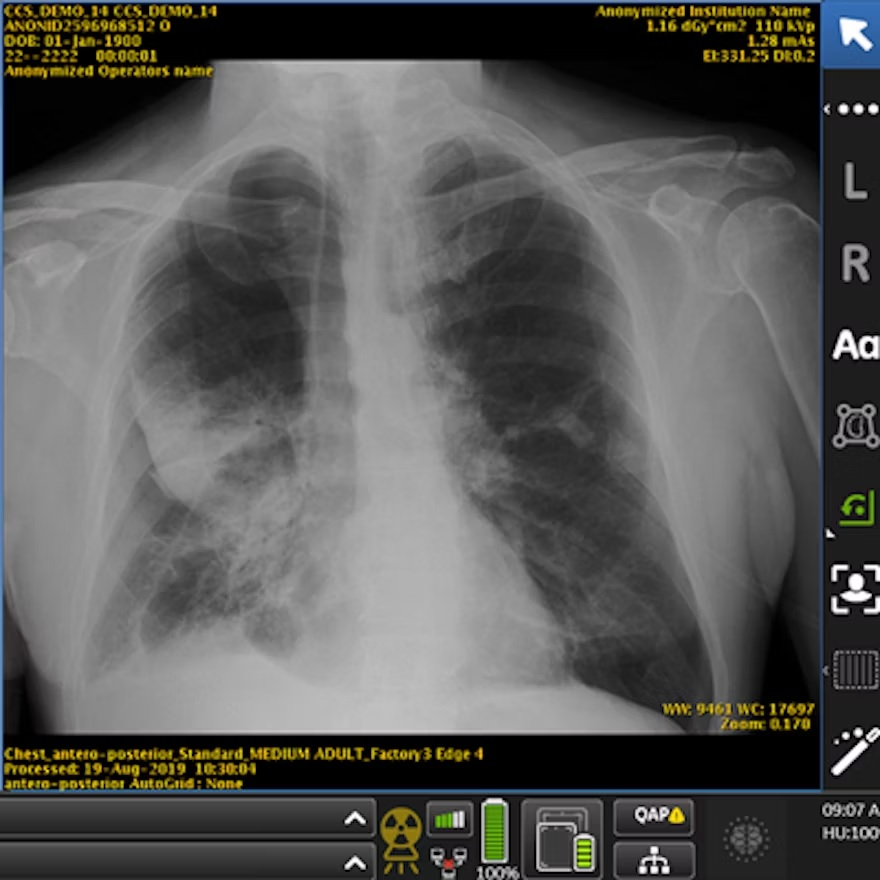

Chest x-ray examples of (A, C) local (feature-based) AI explanations and (B, D) global (prototype-based) AI explanations from a simulated AI tool, ChestAId, presented to physicians in the study. In all examples, the correct diagnostic impression for the radiograph case in question is “right upper lobe pneumonia,” and the corresponding AI advice is correct. The patient clinical information associated with this chest radiograph was “a 63-year-old male presenting to the emergency department with cough.” To better simulate a realistic AI system, explanation specificity was changed according to high (i.e., 80%−94%) or low (i.e., 65%–79%) AI confidence level: bounding boxes in high-confidence local AI explanations (example in A) were more precise than those in low-confidence ones (example in C); high-confidence global AI explanations (example in B) had more classic exemplar images than low-confidence ones (example in D), for which the exemplar images were more subtle.